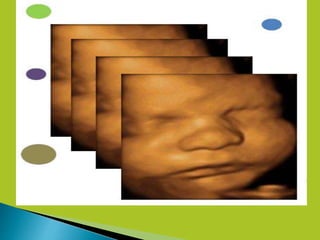

4D ultrasound is a medical

ultrasound technique, often

used in obstetric

ultrasonography (during

pregnancy), providing

4 dimensional images of

the fetus.